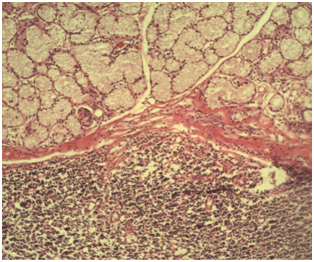

The patient was suggested to undergo tonsillectomy. Routine preoperative investigations were within normal limits and total surgical excision of the lesion through bilateral tonsillectomy was performed under general anesthesia. After completion of the tonsillectomy, both the specimens from the right and left tonsils measured approximately 3,5 cm x 2 cm x1.5 cm. Gross examination revealed a grey, irregular surfaced and 1x0,5 cm measured mass on the midline of left side tonsil (Figure 1). No other lesion was seen on the examination of the contralateral tonsil. Histopathologic examination of the left side revealed tonsilar tissue with chronic inflammation and lobules of mucous secreting salivary acini with ducts adjacent (HSG tissue) and musculary fibers to the surface squamous epithelium of the tonsilar tissue (Figures 2) (Figure 3). Histopathologic examination of the right side revealed only tonsilar tissue with chronic inflammation. A diagnosis of HSG in relation to tonsils was given. Postoperative period was uneventful and recovery was good. A year follow-up revealed no evidence of recurrence and no new relevant symptoms.

Figure 2 Tonsillar tissue with adjacent islands of heterotopic mucinous salivary gland acini (Histopathologic examination, H&E stain, Magnifications: ×100).